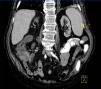

An 81-year-old male with high blood pressure, class II obesity, chronic ischaemic heart disease, severe hyperparathyroidism and end stage renal disease due to nephrosclerosis on HD for two months. He presented with acute coronary syndrome and atrial flutter requiring a coronary catheterisation with transcutaneous revascularisation. He was treated with clopidogrel, carvedilol, amiodarone, transdermal nitroglycerin, esomeprazole, paricalcitol and epoetin alpha, to which acenocoumarol was added. After 15 days, he developed severe intradialytic hypotension and 24 hours later, he experienced abdominal pain and hypotensive syncope with rectal bleeding and he required hospitalisation. The blood test results displayed: haemoglobin: 7.7g/dl, leukocytes: 10.50 10e3/µl, INR: 3.23, CRP: 315.7mg/l and the rest was normal. A computerised tomography was carried out on the abdomen, displaying severe calcific atherosclerosis of the aorta with an absence of occlusion in mesenteric arteries, diffuse oedema of the terminal ileum, ascending colon and caecum submucosa, and pneumatosis intestinalis (Figure 1). He became haemodynamically stable and we administered parenteral nutrition and broad-spectrum antibiotics. After 9 days, he developed a second episode of rectal bleeding. A colonoscopy was carried out and it displayed extensive fibrinous necrotic plaque in the caecum and mucous haemorrhagic suffusions in the ascending and transverse colon. He remained in hospital for 60 days and he lost 16kg during this period. He was discharged with intradialytic parenteral nutrition, which was maintained for three months. His weight stabilised and his total protein and albumin of 4.9g/dl and 1.8g/dl at the time of discharge increased to 7.1 and 3.8g/dl after six months. Twenty-four months later, he remained on oral supplements and maintained nutritional stability. Another computerised tomography of the abdomen was performed and we observed the disappearance of lesions in the right colon and residual pneumatosis in the ileum. A study of faeces that ruled out protein losing enteropathy was carried out.

Figure 1. Computerised abdomen tomography